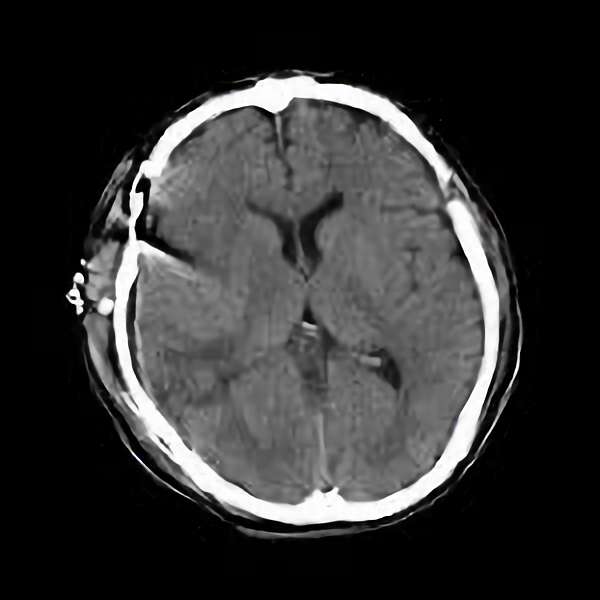

脳血管撮影

手術前

手術後

手術中

モニタリング

手術写真

手術の結果